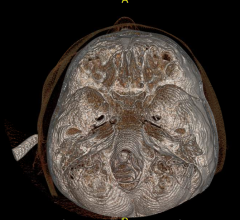

At RSNA 2013, GE will continue to demonstrate its innovations in low dose and high image quality in computed tomography (CT) imaging. The Discovery CT750 HD is the world's first high definition CT (HDCT), built with GE's exclusive Gemstone detector FREEdom Technologies. This allows for intelligent motion correction to “freeze” coronary motion, enhance coronary visualization and obtain additional information on plaque material composition. New this year is kV Assist, which provides optimized personalized scan settings and applications with automated kV and mA selection. kV Assist combined with SnapShot Assist deliver the desired image quality at the lowest possible dose and workflow optimizations for efficient cardiac CT.